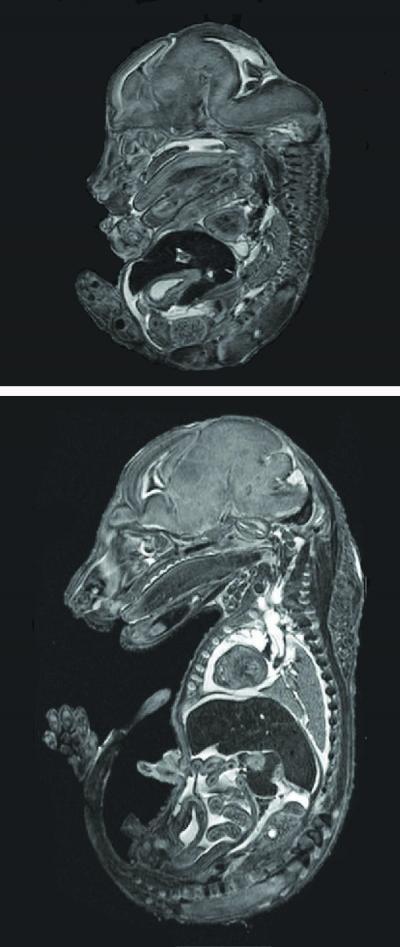

At each of those intervals, Xi Tian, recent Penn State doctoral student and now a postdoctoral scholar at the University of North Carolina, Chapel Hill, measured and evaluated fetuses, examining them with light microscopy and magnetic resonance imaging. She was assisted by co-authors Thomas Neuberger, assistant professor of biomedical engineering in Penn State's Huck Institutes of Life Sciences, working with the Penn State's High-Field Magnetic Resonance Imaging Facility, and Kate Anthony, research technician in animal science.

Fetuses from zinc-deficient mice in the study were 38 percent smaller on average than those from the control group fed a diet with zinc included.

(Photo Credit: Penn State)

Magnetic resonance images of two mouse fetuses -- the top is a smaller, malformed one from a zinc-deficient mouse; the bottom is a healthy fetus from a mouse in the control group.